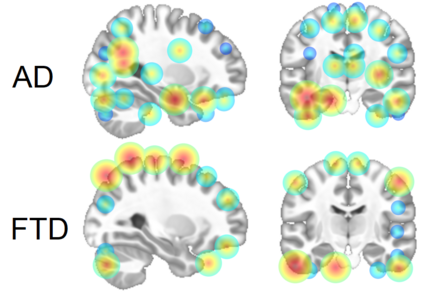

Alzheimer's disease and Frontotemporal dementia are common types of neurodegenerative disorders that present overlapping clinical symptoms, making their differential diagnosis very challenging. Numerous efforts have been done for the diagnosis of each disease but the problem of multi-class differential diagnosis has not been actively explored. In recent years, transformer-based models have demonstrated remarkable success in various computer vision tasks. However, their use in disease diagnostic is uncommon due to the limited amount of 3D medical data given the large size of such models. In this paper, we present a novel 3D transformer-based architecture using a deformable patch location module to improve the differential diagnosis of Alzheimer's disease and Frontotemporal dementia. Moreover, to overcome the problem of data scarcity, we propose an efficient combination of various data augmentation techniques, adapted for training transformer-based models on 3D structural magnetic resonance imaging data. Finally, we propose to combine our transformer-based model with a traditional machine learning model using brain structure volumes to better exploit the available data. Our experiments demonstrate the effectiveness of the proposed approach, showing competitive results compared to state-of-the-art methods. Moreover, the deformable patch locations can be visualized, revealing the most relevant brain regions used to establish the diagnosis of each disease.